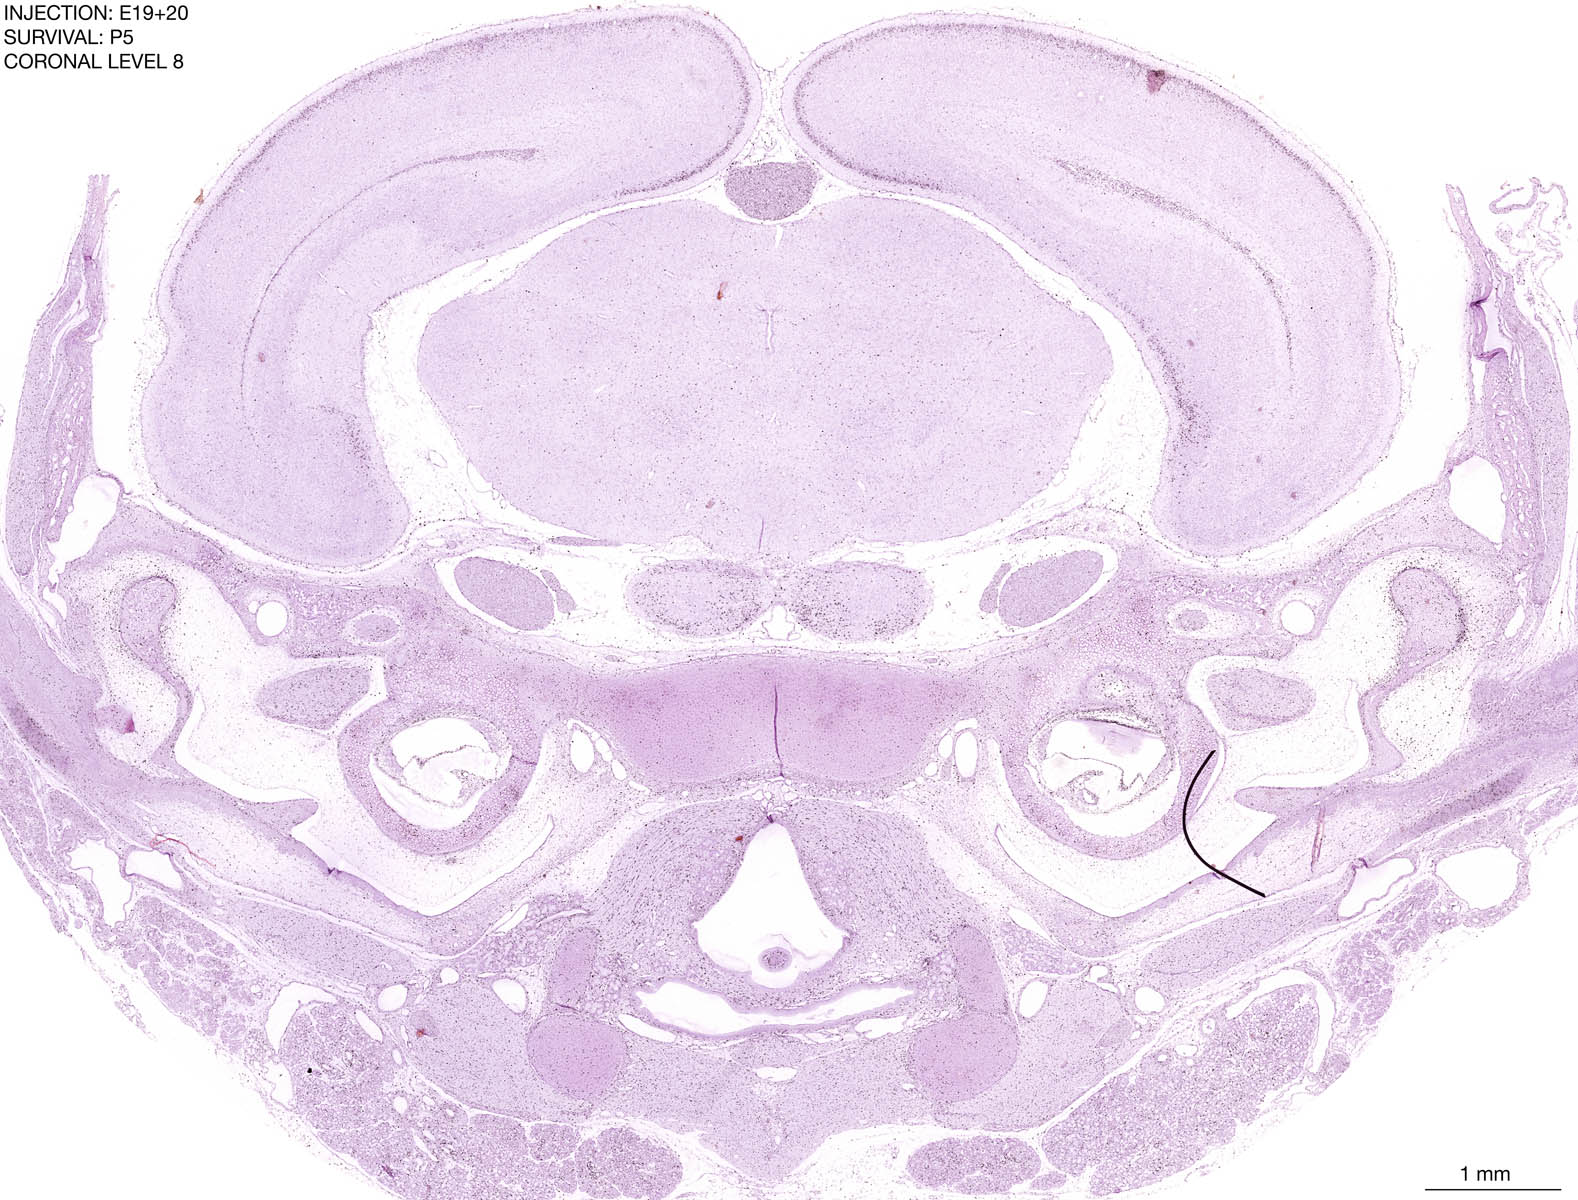

E19+20 P5 Survival The images below are from the brain of a rat that was exposed to tritiated thymidine on E19+20 and survived to P5. Download: Large | High Res Download: Large | High Res Download: Large | High Res Download: Large | High Res Download: Large | High Res Download: Large | High Res Download: Large | High Res Download: Large | High Res Download: Large | High Res Download: Large | High Res Download: Large | High Res Download: Large | High Res Download: Large | High Res Download: Large | High Res Download: Large | High Res Download: Large | High Res Download: Large | High Res Download: Large | High Res Download: Large | High Res Download: Large | High Res Download: Large | High Res Download: Large | High Res Download: Large | High Res Download: Large | High Res Download: Large | High Res Download: Large | High Res Download: Large | High Res Download: Large | High Res